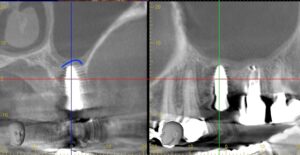

レントゲン画像です。必ずCTで確認をします。

CT画像です。青線部の上顎洞が挙上されているのが

わかります。